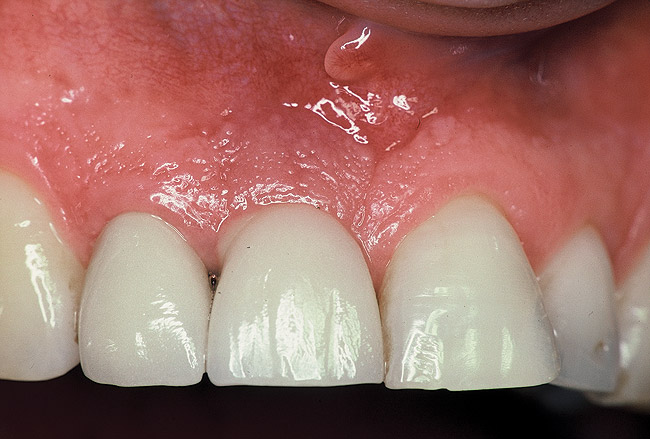

Figure 6  Maxillary right implant-supported restoration exhibiting purulence upon palpation. Bleeding on light probing and 10 mm probing depth was also present.

Figure 6

A 46-year-old man with an unremarkable medical history was referred for evaluation and treatment of the maxillary right central incisor implant. The implant, which had been placed 6 years prior, had never caused any problems until recently, when the patient noted both swelling and soreness at the site. Following 10 days of amoxicillin 500 mg tid, purulence was still present upon palpation of the tissue, and the patient was referred for consultation (Figure 6). Probing attachment loss of 10 mm on the distal aspect and 5 mm on the mesial were measured around the implant. Bone loss was advanced on the periapical radiograph at both the mesial and distal aspects of the hydroxyapatite-coated implant (Figure 7). Full-thickness facial and lingual flaps were reflected to access the implant and surrounding bone, with care taken to preserve the papilla. The defects around the implant on the mesial and distal were 1-wall, and bone loss was present on the direct facial and palatal aspects as well (Figure 8). The surface of the implant was decontaminated, followed by application of enamel matrix derivative. The lesion was filled with freeze-dried bone allograft (Figure 9). The graft-biologic was covered by a flowable polymer barrier (Figure 10). The flaps were coronally advanced and secured with monofilament sutures (Figure 11). The patient was prescribed amoxicillin with clavulanic acid and an oral rinse of 0.12% chlorhexidine during the post-operative period. The healing progressed uneventfully, achieving both a favorable soft-tissue profile and substantial bone fill, as determined radiographically. These results were stable for 7 years (Figure 12 and Figure 13).